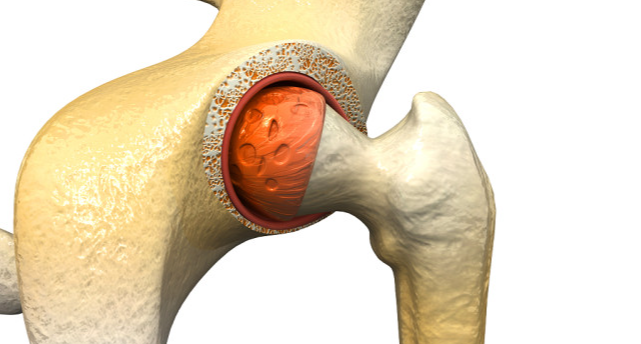

髋关节滑膜炎

图片尺寸640x480